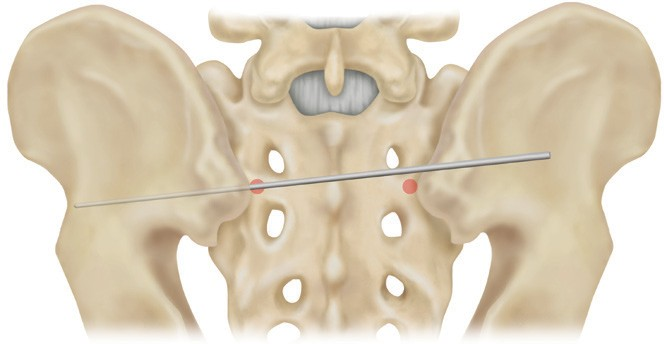

3. 置釘角度

方向朝尾端傾斜20-30°;向內(nèi)傾斜40-50°

開口錐開口后,開路器沿坐骨大切跡內(nèi)向髂前下棘方向走行。探針確保沒有穿破皮質(zhì)骨